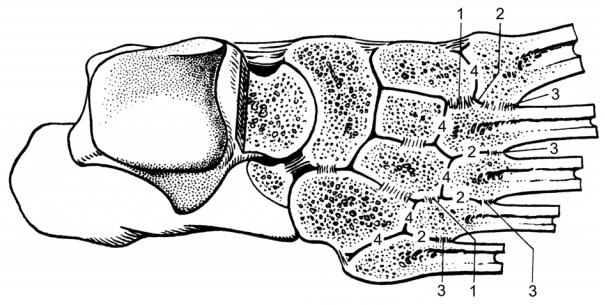

Рис. 36. Суставы и связки правой стопы на горизонтальном распиле

(Feneis H., 1998).

1 – articulatio talocalcaneonavicularis; 2 – articulatio tarsi transversa; 3 – articulatio cuneonavicularis; 4 – ligamenta intercuneiformia interossea; 5 – ligamentum cuneocuboideum interosseum; 6 – articulatio cuneocuboidea; 7 – articulatio calcaneocuboidea; 8 – ligamentum talocalcaneum interosseum; 9 – articulatio subtalaris.